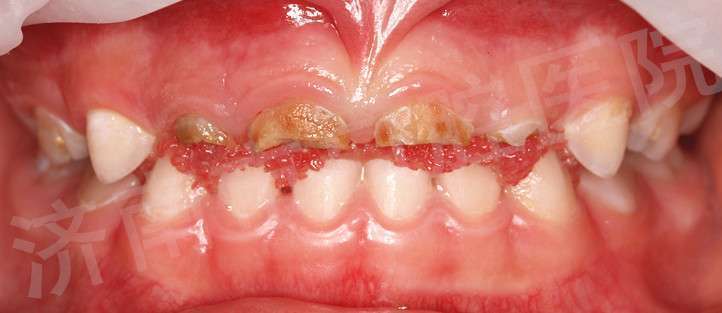

1,重癥低齡兒童齲,不能配合治療者。2,殘障兒童齲,不能配合治療者。 3,患有嚴(yán)重牙科恐懼癥者。 4,牙外傷不能配合治療者。 5,門診不能配合治療,亦不能配合使用笑氣及口服藥物鎮(zhèn)靜的牙病患者。 全麻下一次性牙齒治療前后效果對比

對于年齡很小的小朋友,家長們還要注意一種我們稱之為“喂養(yǎng)齲”也稱“奶瓶齲”的蛀牙。這是低齡兒童齲的一種特殊類型,主要由于不良的喂養(yǎng)習(xí)慣所致,包括:含奶瓶入睡、牙齒萌出后喂夜奶、延長母乳或奶瓶喂養(yǎng)時間、過多飲用含糖飲料等,其在臨床上常表現(xiàn)為下圖的環(huán)狀齲樣子。在寶寶喝完奶后,可以用溫開水給寶寶漱口,能有效清洗、沖走奶液在口腔中的殘渣,保持口腔環(huán)境良好。6個月開始就應(yīng)當(dāng)減少夜奶次數(shù),9個月左右應(yīng)該斷夜奶,讓孩子和大人都能得到很好的休息。